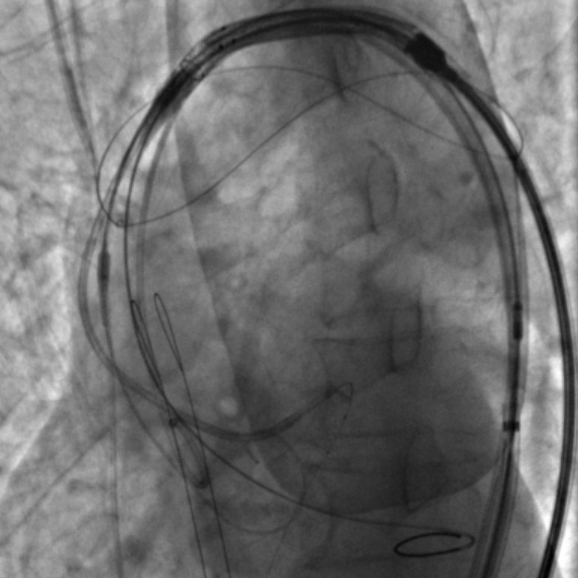

患者既往有COPD病史,且体重极低,为避免麻醉相关并发症,麻醉方式上选择局部麻醉。在左侧股动脉上下两个穿刺点行股动脉穿刺,上穿刺点置入6F鞘管,下穿刺点置入8F鞘管。右侧股动脉切开处送入20F大鞘。沿左股动脉8F鞘,交换送入TriGUARD3™脑保护装置,透视下顺利过弓,准确定位后成功释放过滤器,全部覆盖主动脉弓的三条血管。经TriGUARD3™送入5F猪尾至升主动脉。

沿左股动脉6F鞘,将JL4.0指引导管送至LM开口,送 SION 导丝至前降支远端,循SION导丝依次送Guidezilla II 延长导管和Sprinter 2.5*12m球囊至左冠内进行冠脉保护。

球囊扩张及瓣膜释放

主入路选择20mm预扩张球囊,在起搏器调至180次/分条件下球囊于主动脉瓣膜处进行扩张,扩张效果较满意,球囊可见腰征,无明显反流,左冠显影欠佳。根据预扩情况,决定Downsize选择23号瓣膜,沿Lundquest加硬导丝送入VenusA Plus 23号主动脉瓣膜,起搏器调至180次/分,平稳释放瓣膜。瓣膜释放后主动脉根部造影及冠脉选择性造影提示冠脉通畅,血流TIMI3级,瓣膜位置良好,形态欠佳,同时超声提示存在少-中量周漏,遂使用20mm球囊进行后扩张,扩张后超声显示瓣上最大流速由术前482cm/s,降低至181cm/s ,最大压差由83mmHg降低至13mmHg,平均压差由50mmHg降低至7mmHg,瓣膜形态及位置良好,无瓣周漏。成功撤出 TriGUARD3脑保护装置,并捕获两块脱落组织。手术过程顺利,患者生命体征平稳,手术过程几乎无任何出血。